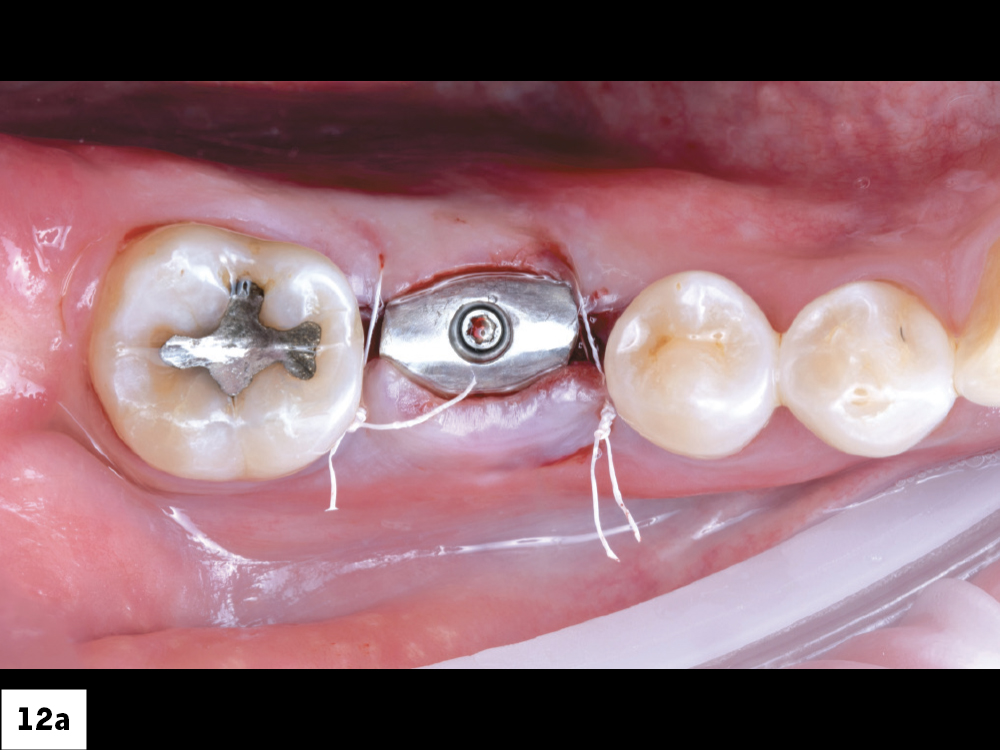

Two Sutures Placed Around the Implant Site

X-Ray of the Fully Inserted Implant Screw

Figures 12a, 12b: Two interrupted sutures were placed using Biotex™ Non-resorbable PTFE Sutures (available through Glidewell Direct), one on the mesial and one on the distal.